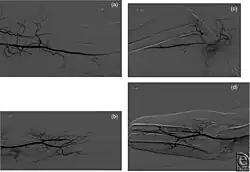

Um dies und weitere Dinge, wie die Venen und/oder Arterien im Arm des Empfängers zu untersuchen, können eine ganze Reihe von Untersuchungen wie etwa die Röntgenaufnahme, die Angiographie, die Doppler-Sonographie, die Phlebographie, oder ein CT durchgeführt werden. Die Ergebnisse dieser Untersuchungen machen die spätere Operation wesentlich besser planbar und können dazu führen, dass eventuelle Probleme schon vorzeitig erkannt werden.[31] Ein solches Problem kann zum Beispiel ein unzureichendes oberflächliches venöses Netzwerk sein, so dass im Zuge der Gefäßchirurgie eine Lösung gefunden werden muss.[32]